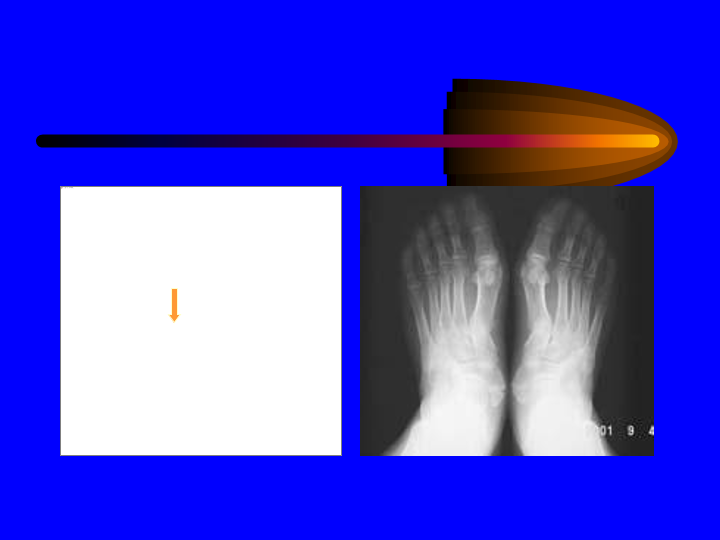

骨和关节X线诊断